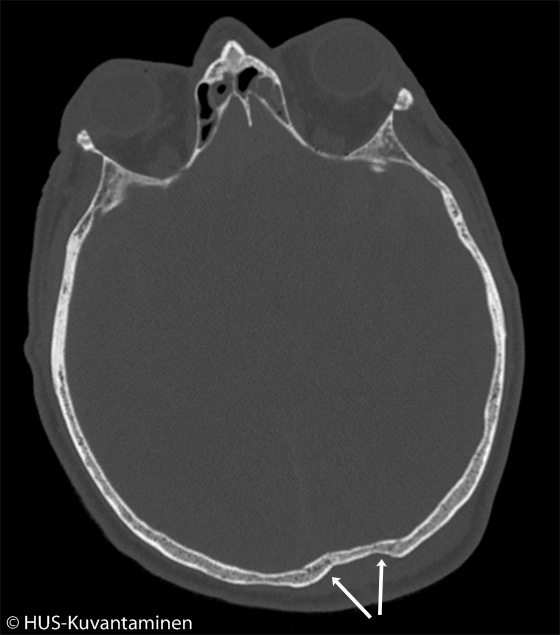

Kallonmurtuma pään TT-kuvassa (kuva 1 löydösmerkinnöin),

Luuikkunalla otetussa pään TT:ssä näkyy impressiomurtuma (nuolet) takana parietaaliluussa, mutta potilaalla ei todettu aivovauriota (ks. myös kuva «Kallonmurtuma pään TT-kuvassa»1

).Kuva: HUS-Kuvantaminen